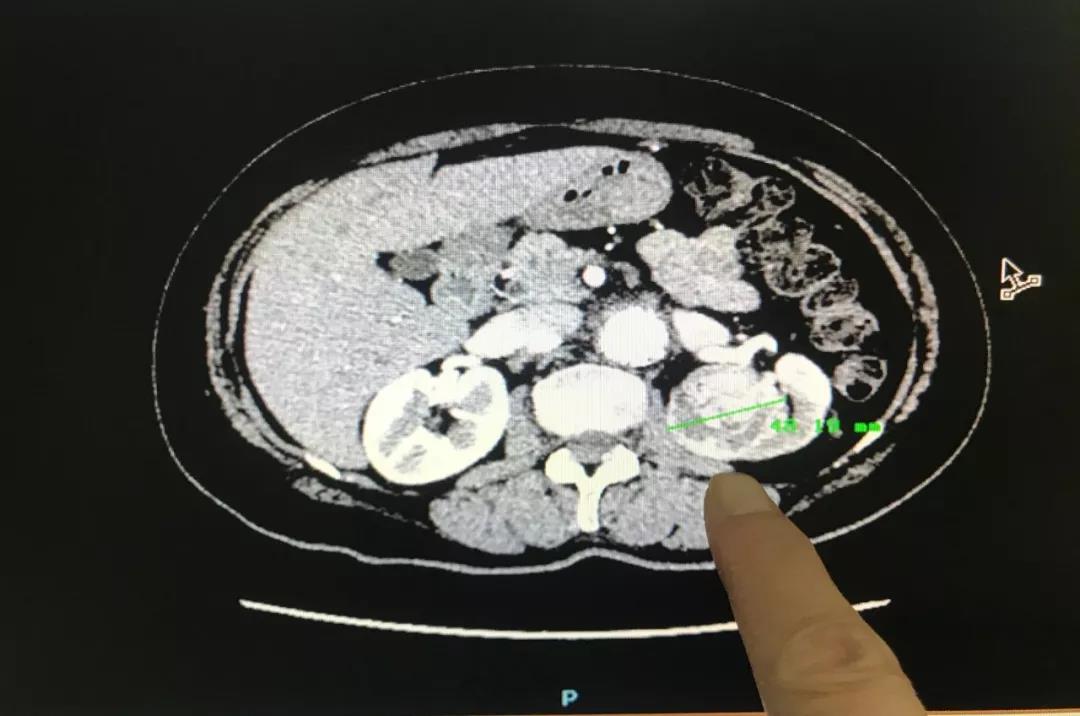

林英立博士接诊后详细询问了王阿姨之前的病史,随即安排了相关检查。“从B超检查结果可以发现肾占位肿瘤已经增长至4.8公分,比原来增大了很多,这并不是一个好的征兆。”